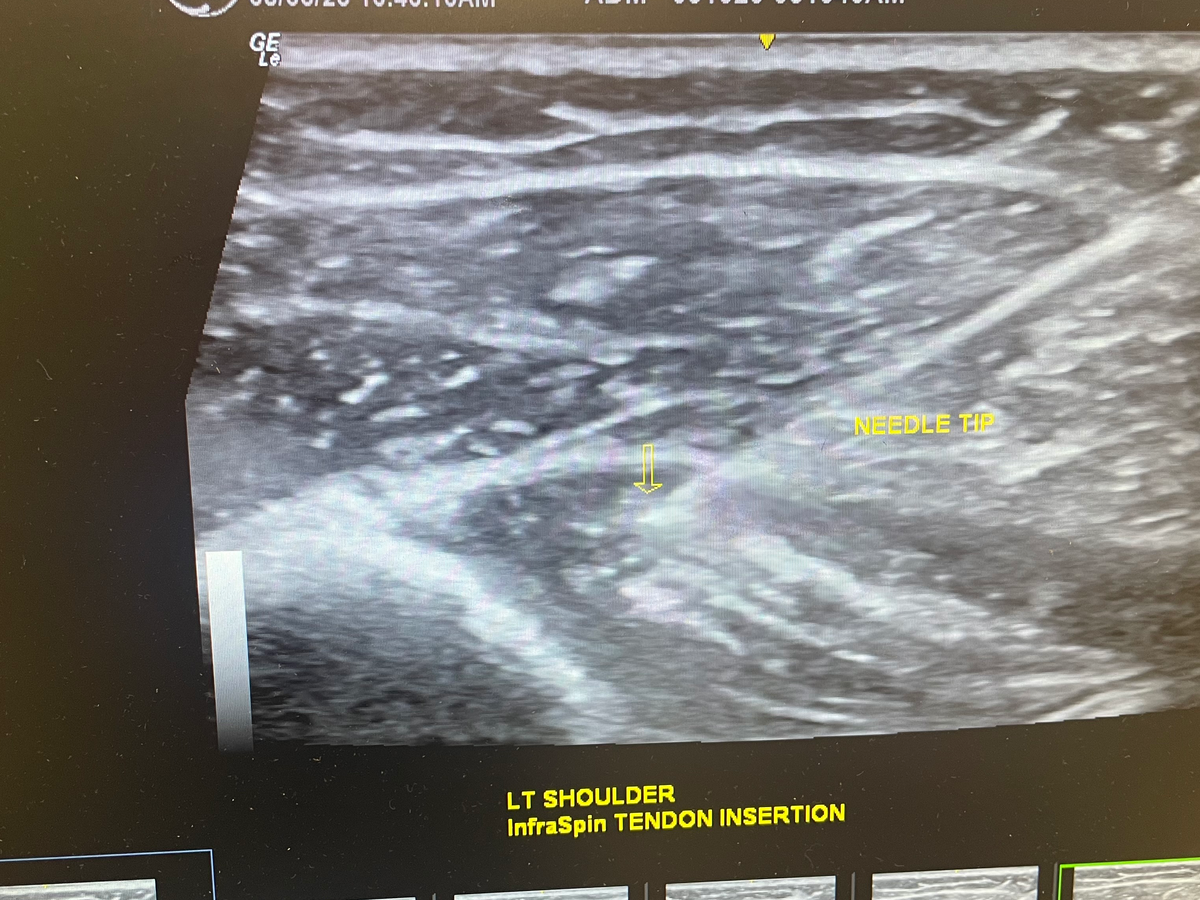

On the 4th of July she was lifted off the ground by her rib cage and tilted and continuously squeezed. Her two ribs 5&6 were popped out and now she is in constant agonizing pain!

These treatments consist of chiropractic rib adjustments and Prolo Therapy injections that only an MD can perform. The treatment will last anywhere from 16-24 weeks weeks!